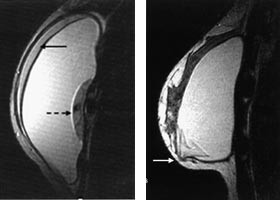

Generelt lader maligne brystkreftsvulster opp intravenøst injiserte MR-kontrastmidler raskere og kraftigere enn godartede svulster og normalt kjertelvev (fig 1). Dette har sammenheng med høyere vaskularitet og økt kapillærpermeabilitet i kreftsvulster sammenliknet med andre typer vev. Tidlige studier rapporterte at brystkreft ble diagnostisert med sensitivitet og spesifisitet på ca. 97 % når en økning i svulstens signalintensitet på 90 % eller mer i løpet av det første minuttet etter kontrastinjeksjon ble brukt som diagnostisk kriterium (11). Med økende erfaringsmateriale er det klart at også mange godartede lesjoner kan lade opp kontrastmiddel raskt og kraftig, særlig gjelder dette enkelte fibroadenomer, fibrocystisk dysplasi og skleroserende adenose (12). Spesifisiteten i senere kliniske MR-studier hvor pasientene har vært utvalgt på bakgrunn av mammografiske og kliniske funn har, avhengig av undersøkelsesteknikk og diagnostiske kriterier, variert fra 37 % til 89 % (13 – 17). Selv om enkelttilfeller av ikke-kontrastoppladende maligne brystvulster er rapportert (18), er den negative prediktive verdien av en MR-undersøkelse som ikke viser kontrastoppladende strukturer i brystet nær 100 %.

Som et resultat av den moderate spesifisitet som oppnås med dynamisk kontrastundersøkelse av brystet, er ulike diagnostiske tilleggskriterier blitt utviklet. Morfologiske egenskaper ved brystlesjonen synes å være vesentlig for å differensiere mellom benigne og maligne svulster. Som ved mammografi er benigne lesjoner ofte velavgrenset med glatte konturer, mens maligne svulster ofte har uskarp avgrensning mot omliggende strukturer og taggete konturer. For at man skal være i stand til å vurdere morfologiske karakteristika optimalt, må bildene ha høyest mulig oppløsning, men da vil bildeopptaket gjerne ta flere minutter, slik at informasjon fra den dynamiske kontrastoppladningen mistes (19). I de fleste studier er det valgt en mellomvei, hvor man ved å bruke en tidsoppløsning på 1 – 2 min og 2 – 3 mm tykke snitt får en akseptabel bildekvalitet for å vurdere morfologiske karakteristika og samtidig et inntrykk av det dynamiske kontrastopptaket i vevet.